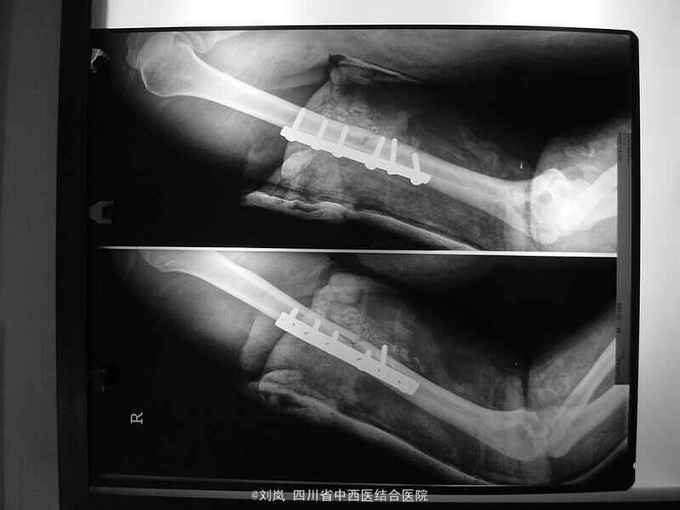

入院诊断: 1、高处坠落伤 2、脑挫裂伤 3、小肠部分坏死 小肠穿孔 肠系膜挫伤 4、右肱骨中段骨折 5、右尺桡骨中下段骨折 6、腹腔积气 7、右第7、8肋可疑骨折 8、轻度贫血 9、全身多发皮肤软组织挫伤 转入诊断: 1、高处坠落伤 2、右肱骨中段骨折 3、右侧尺桡骨中下段粉碎性骨折 4、脑挫裂伤(右,顶叶) 5、右侧桡神经损伤 6、右侧正中神经损伤 7、右侧尺神经损伤 8、右前臂Volkmann缺血性肌痉挛 9、右侧第7肋、左侧第8肋骨骨折 10、小肠部分切除、小肠修补、阑尾切除术后 11、右膝清创缝合术后 12、腹腔积气 13、轻度贫血 14、全身多发皮肤软组织挫裂伤 治疗: 患者急诊入院后,予完善检查,诊断明确,完善急诊手术准备,急诊在全麻下行了“剖腹探查:小肠坏死部分切除、小肠修补+阑尾切除术+腹腔引流术”,术后在ICU继续抗炎、止血、补液脱水监护对症治疗,并请骨科会诊后予右上肢石膏固定。 术后两周外科病情平稳,再次请骨科会诊后转骨科治疗。转入后进一步完善相关检查及术前准备,诊断明确后,在“全麻”下行了"右肱骨中段骨折切开复位内固定、右尺桡骨中下段骨折切开复位内固定术+植骨术、右侧桡神经损伤探查术",术中见桡神经挫伤明显,局部瘀血及增生组织包裹,予松解处理。术后予消肿、止痛、营养神经、预防感染等对症支持治疗,结合针灸、理疗、中药口服及康复治疗。术后伤口愈合及拆线后,予中药熏洗治疗,配合患肢主被动功能康复锻炼,住院2个月,患肢功能活动明显改善,病情好转出院。

随访:出院后定期复诊治疗,继续予药物营养神经、门诊针灸及中药治疗,术后6个月患肢感觉基本恢复正常,功能活动明显改善。 讨论:该患者损伤部位多,创伤重,并发症多,故治疗方案复杂,根据病情需要随时调整治疗重点及治疗方案。神经损伤病情判断及手术探查指征、时间如何把握?